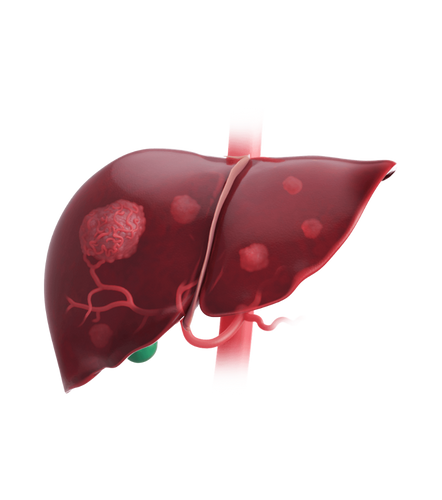

Hepatocellular carcinoma (HCC)

This is the most common type of primary liver cancer, usually seen in people with cirrhosis or chronic hepatitis. It often requires surgery, transplantation, or advanced therapies.

Metastatic tumors

Cancers from other parts of the body (like the colon, breast, or lungs) can spread to the liver, appearing as SOLs. These are often multiple and need systemic treatment.